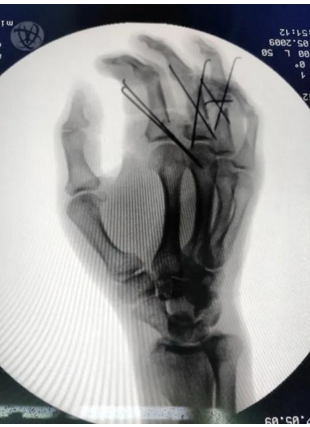

创伤骨科主任钟华介绍,当时权衡利弊后,摒弃了传统的指骨骨折单根骨针纵行固定的方法,采用交叉骨针固定的方式,虽然会增加手术的复杂程度,但是有利于患者术后早期进行功能康复锻炼,有助于患者获得功能良好的再植手。

经过各种外科处理后,终于历时12小时,完成了3处指骨骨折的固定,9条屈指肌腱的修复;并在显微镜下完成5条动脉、6条静脉的吻合、1次前臂浅表静脉血管的移植修复,9条神经的修复,顺利完成了手术。